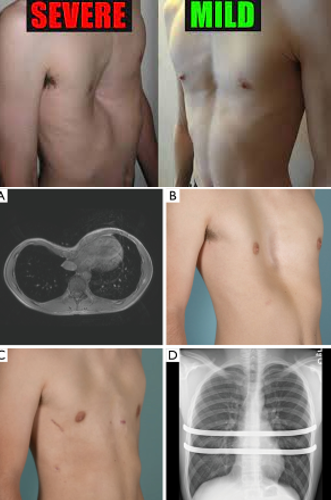

Pectus Excavatum

Funnel-shaped chest:

Depression that sinks inward at the xiphoid process.

Worsens as the child grows.

Cardiac and pulmonary compression can occur in severe cases:

Shortness of breath (SOB)

Exercise intolerance

Surgery may be required if the condition is severe.

Nursing Management:

Perform respiratory assessments.

Provide wound care postoperatively if surgery is done.

Manage pain effectively.